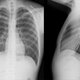

Radiología convencional

Por Roentgen, de forma accidentada, al observar fluorescencia de una pantalla de platinocianuro de bario, después de pasarla por un tubo de rayos X

En este documento Roentgen describió la generación de los rayos X